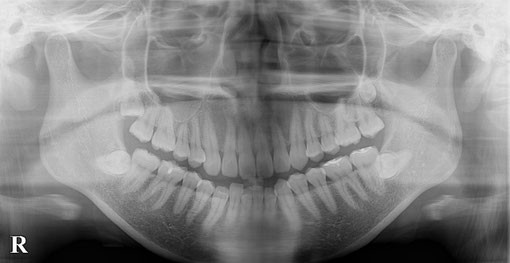

X線写真のように萌出する場所がない「親知らず」は手前の歯を強い力で押しています。その結果、前方の歯列の乱れを生じることがあります。一度乱れた歯は元には戻りません。

親知らずが手前の大臼歯の歯根部に食い込み、大きなむし歯をつくってしまったX線像です。結局手前の大臼歯の神経をとりました。残念です!